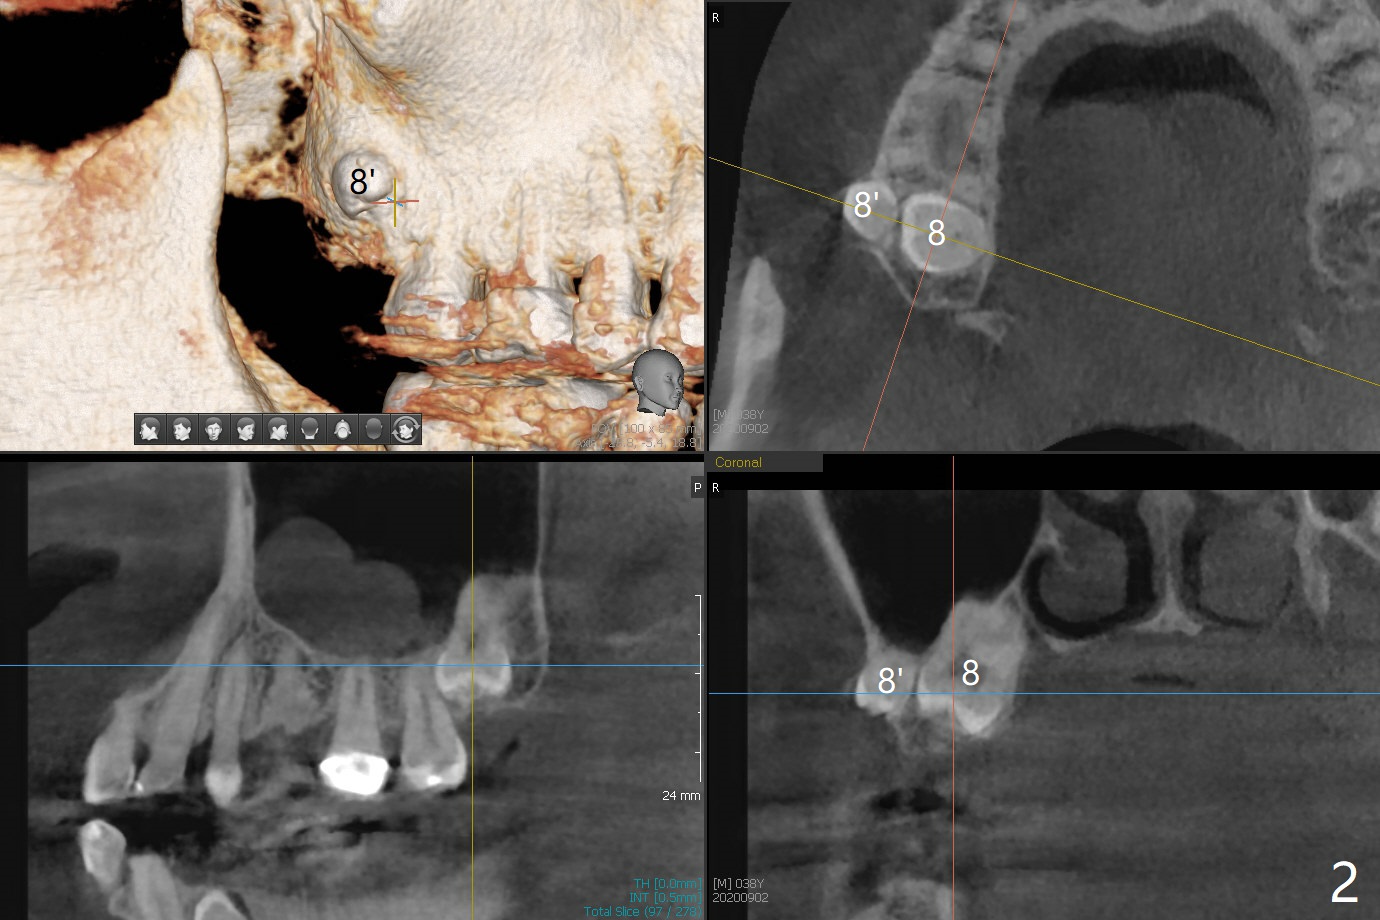

38岁男,十几岁左下4在台湾做根管治疗,八年前外州美国牙医重做根管治疗,他成为我们病人约五年,根尖阴影一直存在,由于无症状,没有引起重视。不过近半年主诉左下唇偶尔麻木,全景片似乎显示左下4根尖阴影相当大,今天CT检查证实这一点(图一),仿佛是根尖囊肿;右下前磨牙区多生牙(*),右上8颊侧也有一个多生牙(图二:8')。虽然病人恐惧手术,但是他不愿意去看专家。尽管囊肿大,累及邻牙,尤其是左下三(图三(可能死髓,Endo Ice; Electric Pulpal Tester;根管治疗)),但是首先做根尖半月形切口,做比较大的根尖切除术,试图刮治囊肿。如果手术当时刮治不全,拔除患牙,增加视野,彻底刮治,填入大量粘性骨块(图四:红圆圈),覆盖PRF膜,缝合,牙周敷料。由于工作需要,病人说他不能没有牙,如果可能,做即刻植牙(图四:绿色),即刻无咬合修复。准备Collagen or Osteogen Plugs,压迫止血。